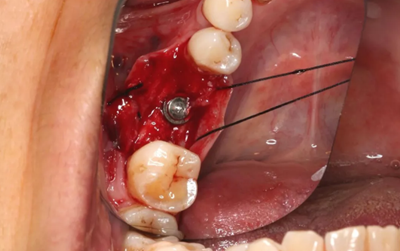

由于取骨致窩洞較大,加之缺牙間隙大,只好選擇植入5mm直徑種植體;種植備洞完成后,頰側(cè)骨壁厚度僅約1mm。

(攝于2017年4月14日)

植入國(guó)產(chǎn)威高(WEGO)5.0×11mm種植體,檢查種植體位于理想軸位。